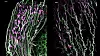

Vev fra klitoris (t.v.) og penis (t.h.) under mikroskopet. De lilla klumpene inneholder endene av nerver. (Foto: Lijun Qi mf., Nature)